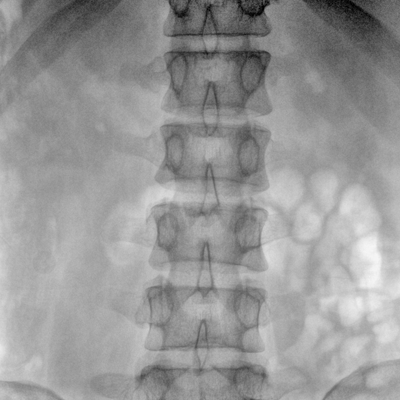

臨床適用科室:骨科、普通外科、矯形外科、創(chuàng)傷外科、泌尿外科、脊柱外科、疼痛外科、消化科、婦科等科室。

大尺寸動(dòng)態(tài)平板探測(cè)器,高DQE、低噪聲、圖像清晰。采用多分辨率圖像增強(qiáng)處理技術(shù),不同部位不同圖像處理算法,滿足客戶多樣化的需求。

采用智能變頻脈沖透視技術(shù),優(yōu)化圖像質(zhì)量的同時(shí)降低輻射劑量,呵護(hù)醫(yī)患健康